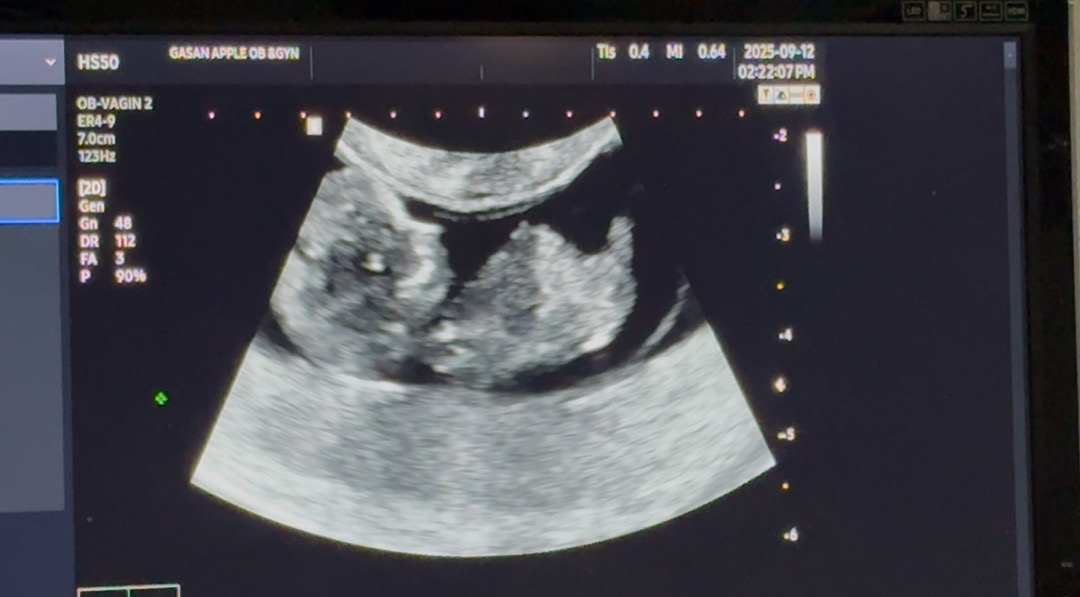

10주 5일차 아기 초음파 보고 왔어요!

10주 5일차 아기 초음파 보고 왔어요ㅎㅎ 엄청 활발하게 움직여줘서 너무 귀엽고 웃기더라구요ㅋㅋㅋ처음엔 다리랑 가랭이만 보여줬다가 몸 뒤집어서 옆모습 보여주고ㅋㅋㅋ또 그새 등돌려버리고ㅋㅋㅋㅋ의사쌤도 애기가 활발하다고 하시더라구요ㅜㅜ 귀욤ㅠㅠ 아들일지 딸일지… 12주차에 기형아 1차 검사 or 니프티검사 둘 중에 뭘로 하고 싶은지 고르라는데..니프티검사가 훨씬 좋나요..? 성별도 바로 알 수 있다고 하던데 다들 어떻게 받으시나용…?